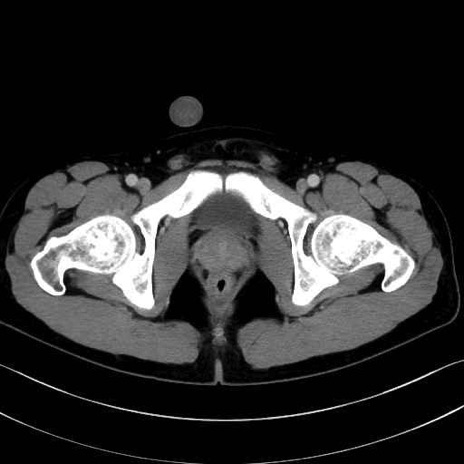

長内転筋(Adductor longus muscle)のCT画像の解剖

長内転筋 (Adductor longus)